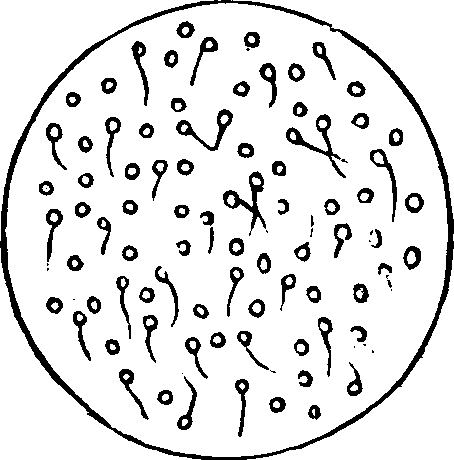

Chronic inflammation of the vagina also gives rise to acrid secretions, which destroy the vitality of the spermatozoa. Suppression of the menses, or any disorder of the uterine functions, may disqualify the female for reproduction. Flexions of the uterus, displacements, congestions, and local debility, may likewise prevent fertility. Sterility may result from impaired ovarian innervation or undue excitement of the nerves, either of which deranges the process of ovulation. Even too frequent indulgence in marital pleasures sometimes defeats conception. Prostitutes who indulge in excessive and promiscuous sexual intercourse, seldom become pregnant. Any thing that enfeebles the functional powers of the system is liable to disqualify the female for reproduction.